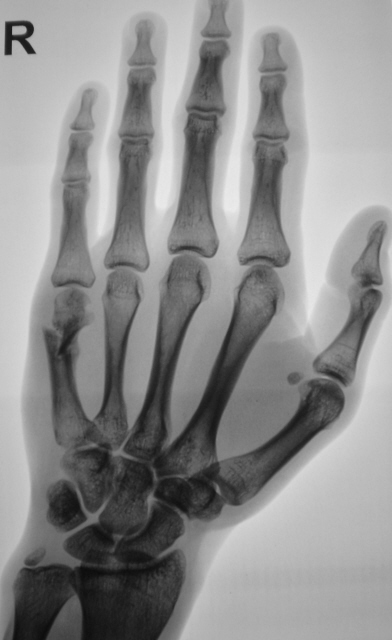

Катенёв Валенти... Дата публикации 02.12.2009, 22:30 Можно ли представленное рассматривать, как консолидированный перелом и выписывать пациента "к труду"? 1..VOPROS...JPG 2..VOPROS...JPG 3..VOPROS...JPG 4..VOPROS...JPG ВложениеРазмер 1..VOPROS...JPG71.9 КБ 2..VOPROS...JPG69.04 КБ 3..VOPROS...JPG77.01 КБ 4..VOPROS...JPG60.22 КБ Чт, 03/12/2009 - 14:39 #1 Глазков Игорь А... Не на сайте Был на сайте: 9 месяцев 2 недели назад Зарегистрирован: 19.12.2008 - 20:41 Публикации: 1597 определяется неправильно сросшийся субкапитальный перелом. Судить о возвращении к труду сложно, потому что , если труд физический, связанный с нагрузкой на кисть, то слабая костная мозоль может "дать трещину". Прийди к Себе Пт, 04/12/2009 - 18:35 #2 Vega Не на сайте Был на сайте: 3 месяцев 1 неделя назад Зарегистрирован: 22.01.2009 - 19:16 Публикации: 1087 Нет Пт, 04/12/2009 - 18:37 #3 Катенёв Валенти... Не на сайте Был на сайте: 7 лет 2 недели назад Зарегистрирован: 22.03.2008 - 22:15 Публикации: 54876 Спасибо Vega! Очень ждал, именно Вашего комментария. Еще раз большое спасибо.

определяется неправильно сросшийся субкапитальный перелом. Судить о возвращении к труду сложно, потому что , если труд физический, связанный с нагрузкой на кисть, то слабая костная мозоль может "дать трещину".